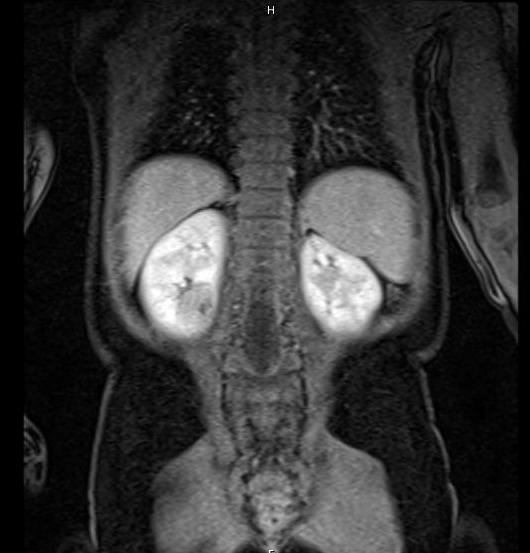

The next best step in management of this child with bilateral renal masses is

The most appropriate management of this patient with bilateral renal masses is